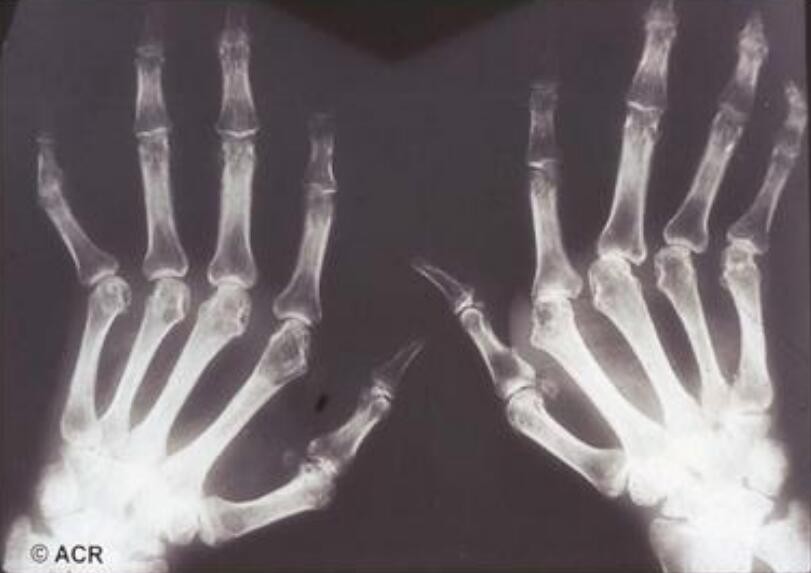

風濕雖然看起來無害,但是一到陰雨天就會讓你疼痛難耐。它是一種侵犯關節、骨骼、肌肉、血管等為主的一種情況,發病時間長且比較隱蔽。那么蜂王漿對于風濕有沒有效果呢?小編帶你了解一下。

風濕吃蜂王漿還是有一定好處的,風濕大多有關節病變和癥狀,會有紅腫、疼痛以及功能受損等多方面炎癥的表現。蜂王漿中的王漿酸有很強的殺菌消炎的作用,可以清除身體內的一些細菌,對于炎癥和紅腫都有一定的緩解作用。